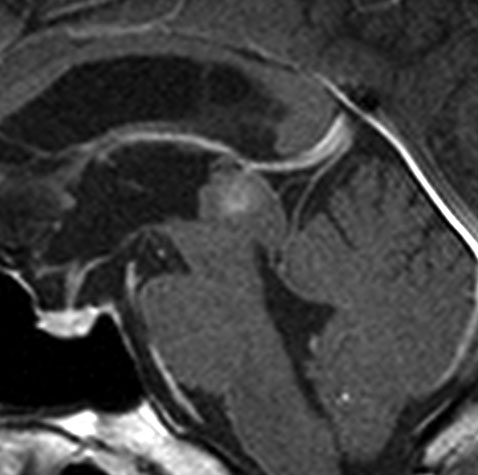

15歳で水頭症で発症して進行した例

手術摘出した方が良い例です。

毛様細胞性星細胞腫であり,基本的には初回手術で全摘出できるのですが,現実的には,技術的に難しすぎるので部分摘出で終えることが多いでしょう。この子は,15歳の時に閉塞性水頭症のために,頭痛,嘔吐,意識障害,瞳孔不同となりました。開頭部分摘出術と第3脳室開窓術で回復して,その後にカルボプラチンとビンクリスチンの化学療法を受けました。

でも腫瘍増大が止められずに,発症1年後に54グレイ30分割の放射線治療を受けています。さらにその半年後くらいから再増大しましたが,スードプログレッションと考えられました。上左MRIは放射線治療前,上右MRIは放射線治療1年後です。毛様細胞性星細胞腫は放射線治療後に一過性増大(多くはのう胞性増大)することが多いです。

のう胞性拡大が止まらず,発症3年後にまた再開頭手術 (left occipital transtentorial approach) で亜全摘出しました。右は術後の画像です。初発時の最初の手術で亜全摘出あるいは全摘出 gross total removalできていればと思える例です。